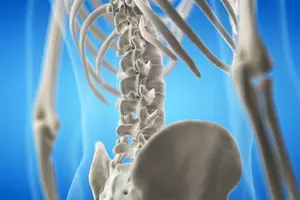

척추측만증은 흔한 질환으로, 척추가 옆으로 휘어지는 것을 의미합니다. 정상적인 척추는 S자 모양으로 약간 구부려져 있지만, 측만증 환자의 경우 이 구부러짐이 10도 이상 심각해집니다. 척추측만증은 누구에게나 발생할 수 있지만, 청소년기에 더 흔합니다. 오늘은 이를 위해 척추측만증 치료법, 증상, 원인, 수술에 대해 알아보도록 하겠습니다.

척추측만증은 척추가 옆으로 휘어지는 척추 기형입니다. 약 100명 중 3~4명이 척추측만증을 가지고 있으며, 대부분의 경우 어린 시기에 발병합니다. 이는 단순한 측만뿐만 아니라, 척추뼈 자체의 회전 변형을 동반하기 때문에 3차원적인 기형 상태라고 볼 수 있습니다. 척추측만증은 심각한 경우 호흡 곤란, 심장 질환, 통증 등의 건강 문제를 일으킬 수 있지만, 조기 발견 및 치료를 통해 정상적인 삶을 살 수 있습니다.

척추측만증 수술 방법에는 척추 뒤쪽 근육을 접근하여 수술하는 후방 수술 방법과, 척추의 앞쪽으로 접근하여 수술하는 전방 수술 방법이 있습니다. 두 방법 중에는 후방 접근 방법으로 수술하는 경우가 더 많습니다.

후방 수술 방법은 척추측만증 수술 중 가장 일반적인 방법으로, 척추 뒤쪽 근육을 박리하여 척추뼈를 노출시킨 후 금속 나사와 막대로 척추를 교정합니다. 이 수술 방식은 수십 년 동안 사용되어 왔기 때문에 안정성이 높습니다. 특히, 한쪽만 심하게 휘어진 경우(단만곡)이나 여러 방향으로 휘어진 경우(복합만곡)에 효과적입니다. 견고한 금속 나사와 막대를 사용하여 척추를 교정하기 때문에, 교정 효과가 오래 지속됩니다.

전방 수술 방법은 복강을 통해 척추 앞쪽에 도달하여 척추뼈를 교정하는 방법입니다. 후방 접근법에 비해 덜 침습적이지만, 모든 측만증 유형에 적용 가능한 것은 아닙니다. 이 수술 방식은 근육 손상이 적어 회복이 빠르며, 필부 절개가 작고 통증이 적습니다. 흉관 변형이 심한 경우, 흉곽을 직접 교정할 수 있어 효과적입니다.